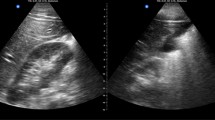

Agreement between trainee and cardiologist was moderate for interpretation of tricuspid valve regurgitation; fair for aortic regurgitation and mitral valve regurgitation; slight for LV dysfunction; and poor for the presence of mitral stenosis and pericardial effusion. Additional file 3: Figure S3 through Additional file 5: Figure S5 are examples of trainee-obtained images that were of sufficient quality to be interpretable, yet the trainee did not detect a pathology that was present based on the cardiologist’s interpretation. Scans from eight patients showed a pericardial effusion, but none were detected by trainees. Among 34 patients with LV dysfunction, 18 (52.9%) were interpreted as such by trainees, and among 319 patients with normal LV function, 73 (22.9%) were incorrectly interpreted by trainees as having LV dysfunction. By trainee, mean kappa values across the 6 key pathologies ranged from 0 (no agreement) to 0.32 (fair agreement) (Fig. 2b). There was a significant association between score on the post-training 20Q Ultrasound Images assessment and mean kappa value across the 6 key pathologies in univariate analysis (p = 0.004).

Additional file 3. Figure S3:

Example image: image quality sufficient for detection of tricuspid regurgitation, but abnormality not detected by trainee.

Additional file 4. Figure S4:

Example image: image quality sufficient for detection of aortic regurgitation, but abnormality not detected by trainee.

Additional file 5. Figure S5:

Example image: image quality sufficient for detection of aortic regurgitation, but abnormality not detected by trainee.